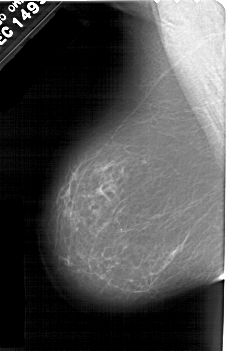

FILE: A_1601_1.RIGHT_CC.OVERLAY

TOTAL_ABNORMALITIES 1

ABNORMALITY 1

LESION_TYPE CALCIFICATION TYPE PLEOMORPHIC DISTRIBUTION LINEAR

ASSESSMENT 4

SUBTLETY 2

PATHOLOGY BENIGN

TOTAL_OUTLINES 1

BOUNDARY